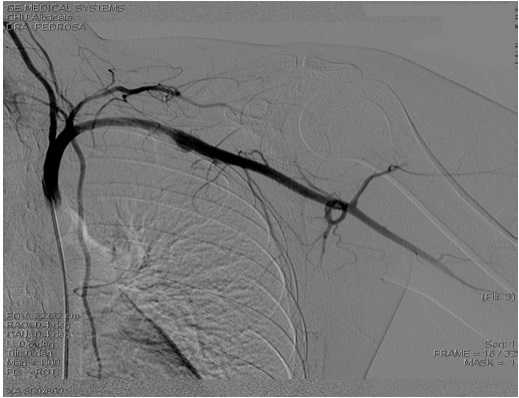

Respecto a las exploraciones complementarias (Figuras 1 y 2), se realizó angio-TAC, donde se informa que visualiza un aneurisma subclavio izquierdo de aproximadamente 2,6 x 1,9 x 1,2 cm, (CC x T x AP), en la porción proximal de la arteria, por detrás de la clavícula. Se indica presencia de arcos costales bilaterales, observando en el lado izquierdo una neoarticulación entre la costilla cervical y la primera costilla que junto a la clavícula pinzan el espacio vascular, como probable causa de la formación aneurismática. No se objetiva correcto llenado de los vasos radiocubitales desde la flexura del codo aproximadamente. Ante estos hallazgos, se realiza arteriografía donde se confirma la presencia de dilatación aneurismática subclavia izquierda, a nivel de zona de compresión costoclavicular, con permeabilidad subclavio-axilar, observando defecto de llenado humeral proximal, con visualización de dos arterias humerales con trombo en ambas, la más medial a pesar del trombo proximal presenta paso distal con relleno radial.